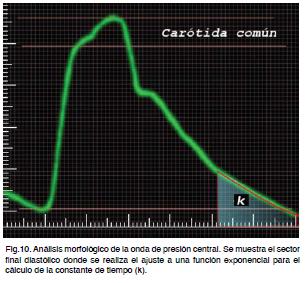

Basándose en modelos teóricos se utiliza el sector diastólico final de la curva de presión arterial carotídea. Dicho sectorse ajusta a una función monoexponencial calculándose la constante de tiempo (k) correspondiente (Figura 10). Conceptualmente, cuanto mas rápida es la caída de la presión en el sector analizado menor es la constante de tiempo y mayor es la rigidez arterial. Por el contrario, una caída lenta con una constante de tiempo mayor es indicadora de buena función de modulación arterial.